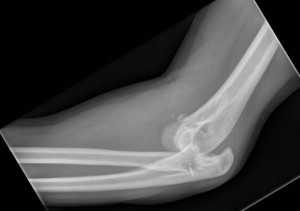

(Слева) На боковой рентгенограмме локтевого сустава визуализируется небольшой отломок перелома кончика локтевого отростка. Края отломка неправильной формы, что отличает это повреждение от несросшегося центра оссификации апофиза.

(Справа) На боковой рентгенограмме у ребенка после падения определяется косой перелом через среднюю точку локтевого отростка с незначительным смещением. Напротив, зона роста локтевого отростка волнистая с выраженным кортикальным слоем по краям. (Слева) На боковой рентгенограмме локтевого сустава после падения на вытянутую руку при согнутом локтевом суставе виден смещенный отломок, оторвавшийся от кончика локтевого отростка. Степень смещения свидетельствует о значительном повреждении трехглавой мышцы.